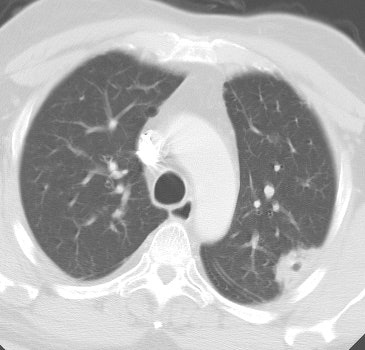

Bronchoalveolar cell carcinoma presenting at multiple poorly marginated lung nodules- some of which appear cavitary. The findings mimic a pulmonary infectious process. |